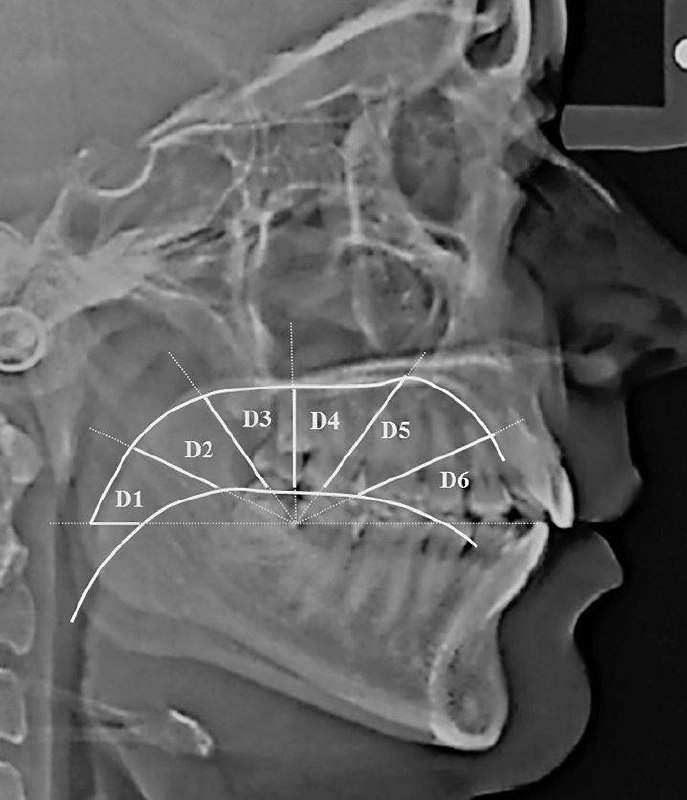

如果舌头抵住上颚,副交感神经系统就会减少全身活动,即心跳和呼吸节律增加。

如果将其放置在软腭上,交感神经系统的活动就会减少。

软腭位置有利于副交感神经的活跃。休息和消化。皮质醇释放减少。除非面临威胁,需要战斗、逃跑、僵住或讨好,否则状态会更好。